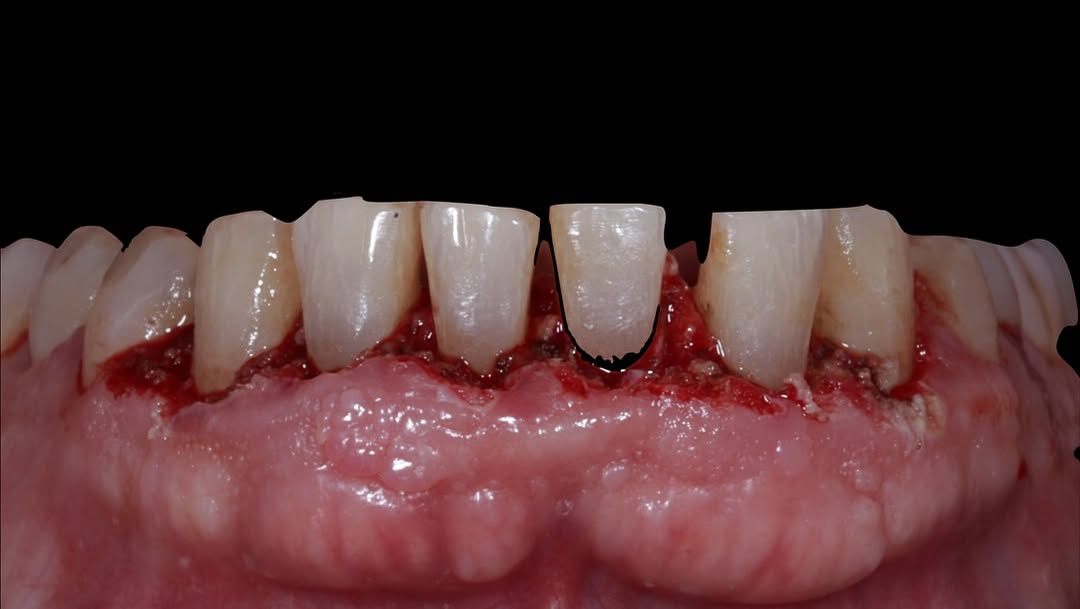

Durante una mañana, asistirás a una Cirugía Mucogingival de recubrimiento radicular de recesiones múltiples en IV y V sextante (36 a 43).

Gracias al uso del microscopio y a la proyección en tiempo real en pantalla, verás exactamente lo mismo que veo yo durante la cirugía, sin tener que estar

Aprende la planificación y técnica de la cirugía Mucogingival para el recubrimiento de recesiones y aumento de banda queratinizada en el sector anteroinferior

Durante una mañana, asistirás a una Cirugía Mucogingival de recubrimiento radicular de una recesión unitaria en 31 con frenillo asociado. Gracias al uso del microscopio y a la proyección en tiempo real en pantalla, verás exactamente lo mismo que veo yo durante la cirugía, sin tener que estar